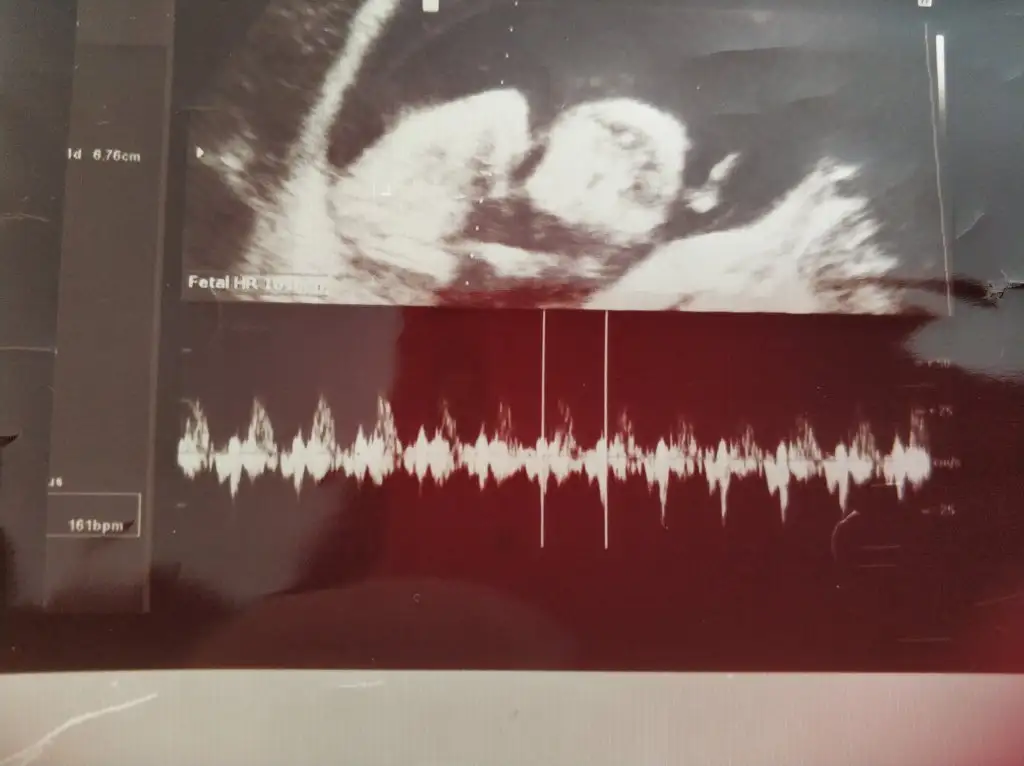

bu benim kizim cikinti gayet net ve ortada ve ben kizim diyooo